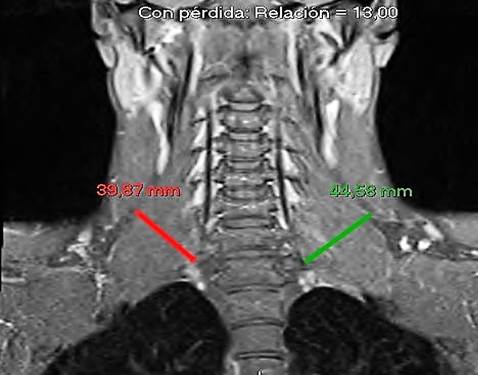

Las imágenes no demostraron lesiones ocupantes de espacio o arco costal accesorio que realizaran compresión extrínseca del drenaje venoso. Ante la no identificación del origen etiológico del cuadro actual que aquejaba el paciente se realiza una resonancia magnética nuclear (RMN) con reconstrucción en tres dimensiones de cuello en el que se evidenció hipertrofia de escalenos bilateral que comprimían el sistema venoso local, de predominio izquierdo confirmando el diagnóstico de síndrome de Paget-Schroetter (Figura 2).

En el caso presentado el diagnóstico imagenológico inicial se obtuvo por medio de ecografía de tejidos blandos y doppler color. Así mismo se realizó RMN de cuello en donde se corroboró la hipertrofia de escalenos, sobre todo izquierdos, que favorecieron la formación del trombo por efecto compresivo local.